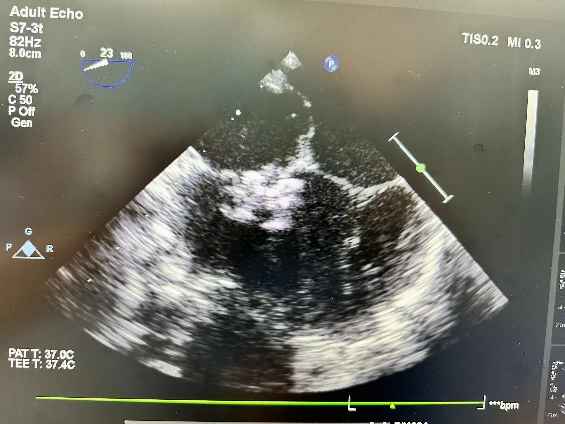

手术中,在王安彪主任医师指导下,在超声科朱梅、梁皓主任医师实时超声引导下,訾捷主任医师,张杰、钟京涛主治医师仅用时20分钟,就将全降解封堵器准确释放,成功修补了两位小朋友室间隔缺损,术后超声结果显示手术效果达到预期。